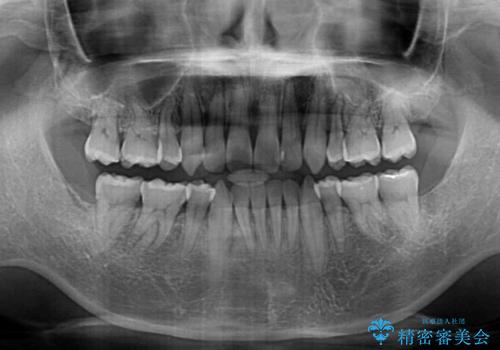

- 口元の閉じにくさと、前歯のでこぼこの歯並びを気にして来院された患者様です。

口元を積極的に引っ込めるために、上下左右の小臼歯計4本を抜歯することとしました。

叢生が強い場合、抜歯スペースが叢生を解消するために消費されるため、口元の突出感があまり改善されないことがあります。

今回の治療では、奥歯が前方に傾斜した歯並びだったため、奥に起き上がることで歯列が後方に移動し、横側からも口元が引っ込んだ感じが分かるほど改善されました。